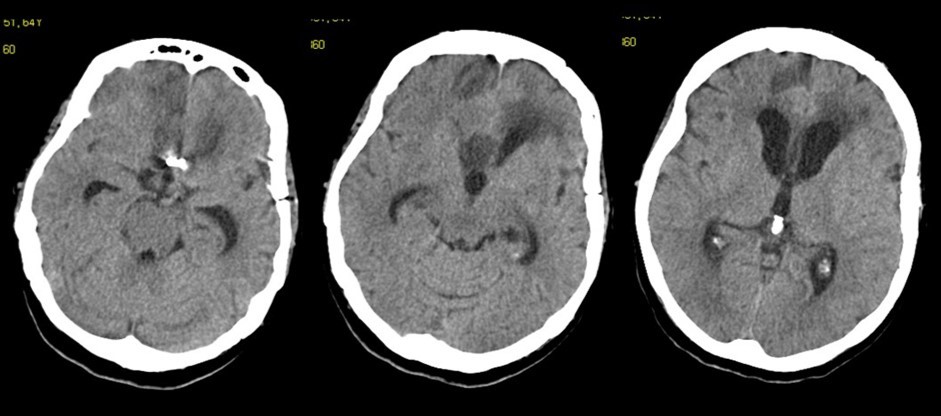

Figure 2.Follow-up at 6 weeks. The vascular clip is in place. Ventricles are quite enlarged. The region of the corpus callosum appears altered

The follow-up CT scan made two weeks later showed a mild ventricular enlargement and persistent density alterations in the frontal region (Figure 2) that were interpreted as normal. Once discharged at home, the patient developed progressive disorientation that finally let her refer to our hospital for consult four months after aneurysm clipping. The cerebral CT we performed showed further ventricular growth, and a tumor-like image in the right frontal lobe (Figure 3). She was admitted to our ward and underwent a contrast-MRI that confirmed the suspicion of aggressive intra-axial neoplasm (Figure 4). The week after, under general anesthesia we performed a right craniotomy and removed a large part of the tumor, sparing the portion going through the corpus callosum (Figure 5). During convalescence the patient had few epileptic attacks, treated with drugs. A mild cognitive impairment persisted after surgery, without focal motor deficits. The gait, limited and unstable since the SAH, remained poor and the patient never walked again after the operation. The histological examination indicated a WHO grade IV glioma: IDH1-p53 negative glioblastoma. The patient and her relatives refused a ventriculo-peritoneal shunt after knowing this unfortunate diagnosis. Transferred to rehabilitation, the woman made just a short low-dose chemotherapy cycle and finally died four months after tumor resection.

The clinical and radiological features of these two diseases are perfectly known to neurosurgeons; anyhow our case shows that trouble rises when they do occur simultaneously. The patient we described had initially acute signs due to SAH and later signs that were incorrectly interpreted as SAH-related. The tumor was almost invisible -because of its likely small volume and thick SAH- in the first CT performed (Figure 1). Analyzing the early follow-up CT (Figure 2) anyway things do not seem so clear. In the frontal region remained too much fogging close to the midline; the asymmetric distribution of such alteration should had point out a problem, but everybody kept thinking to a “simple” post-hemorrhagic condition, due to ventricular enlargement and focal ischemia. The initial mental impairment of that period was equally attributed to a normal SAH result with moderate hydrocephalus. The proper diagnosis of glioma happened late, and the patient was at that point unable to have significant benefits from surgery.